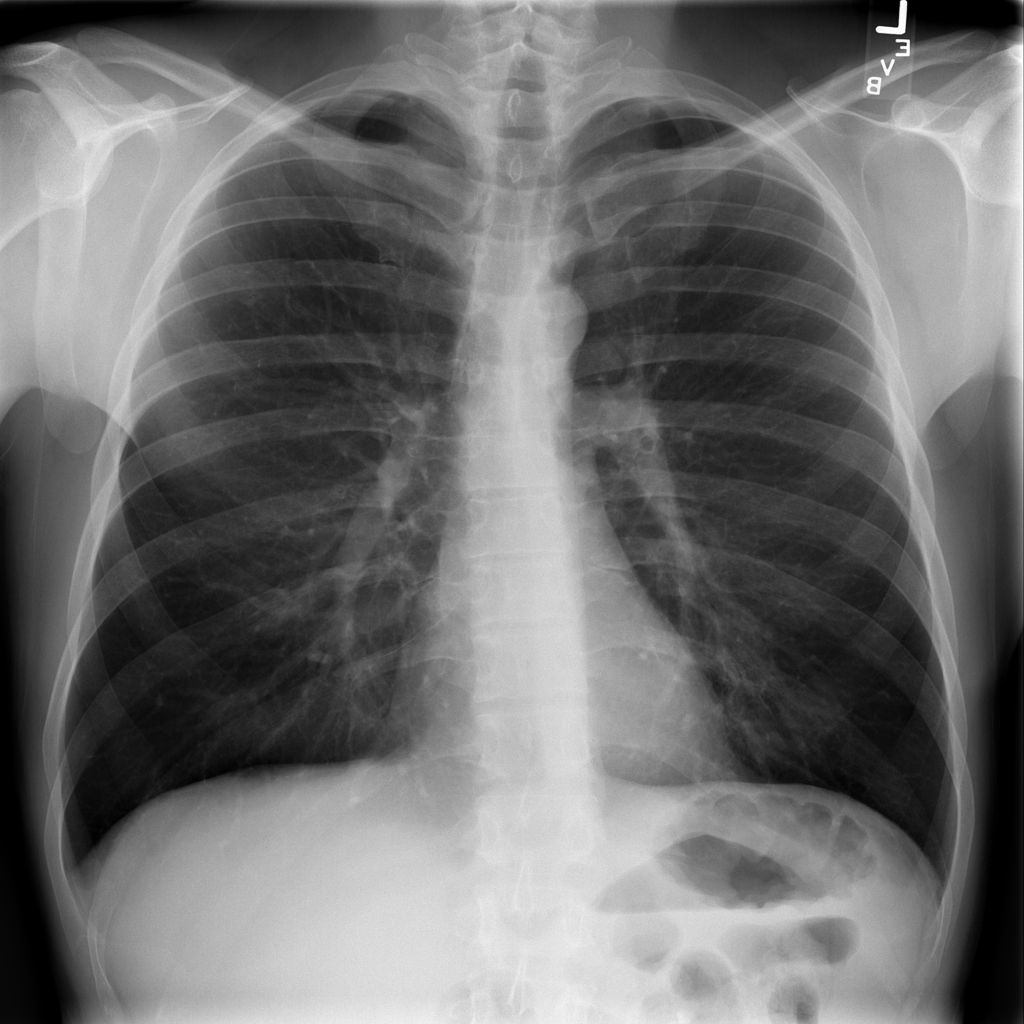

Pneumonia

Pneumonia is an infection of the lung tissue, often caused by bacteria, viruses, or less commonly fungi. On chest X-ray it can appear as focal or patchy air-space opacity, though imaging alone does not always prove the cause.

Showing up to 90 reference images for Pneumonia.

PAT-B3C3 · IMG-001Pneumonia

PAT-B3C3 · IMG-001

PA